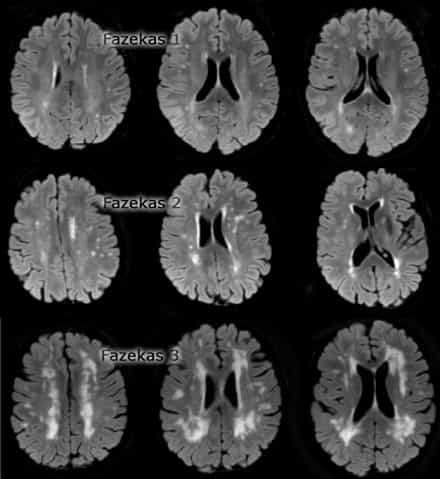

The Fazekas qualitative scale (Fig. 3) is the most widely used system to determine the magnitude of white matter lesions in MRI and it ranges as follows:

– degree 0: absence of injury;

– degree 1: existence of focal lesions;

– degree 2: beginning confluence of foci;

– degree 3: diffuse lesions that cover entire regions.